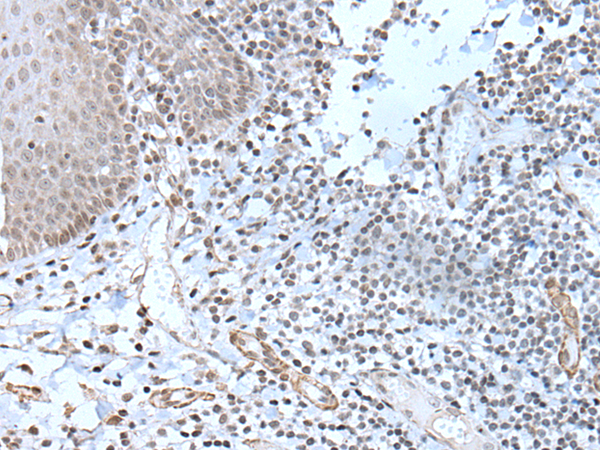

分类: 科研抗体货号: P12841别名: SBF; STAF; pHZ-1应用: IHC反应种属: Human, Mouse, Rat